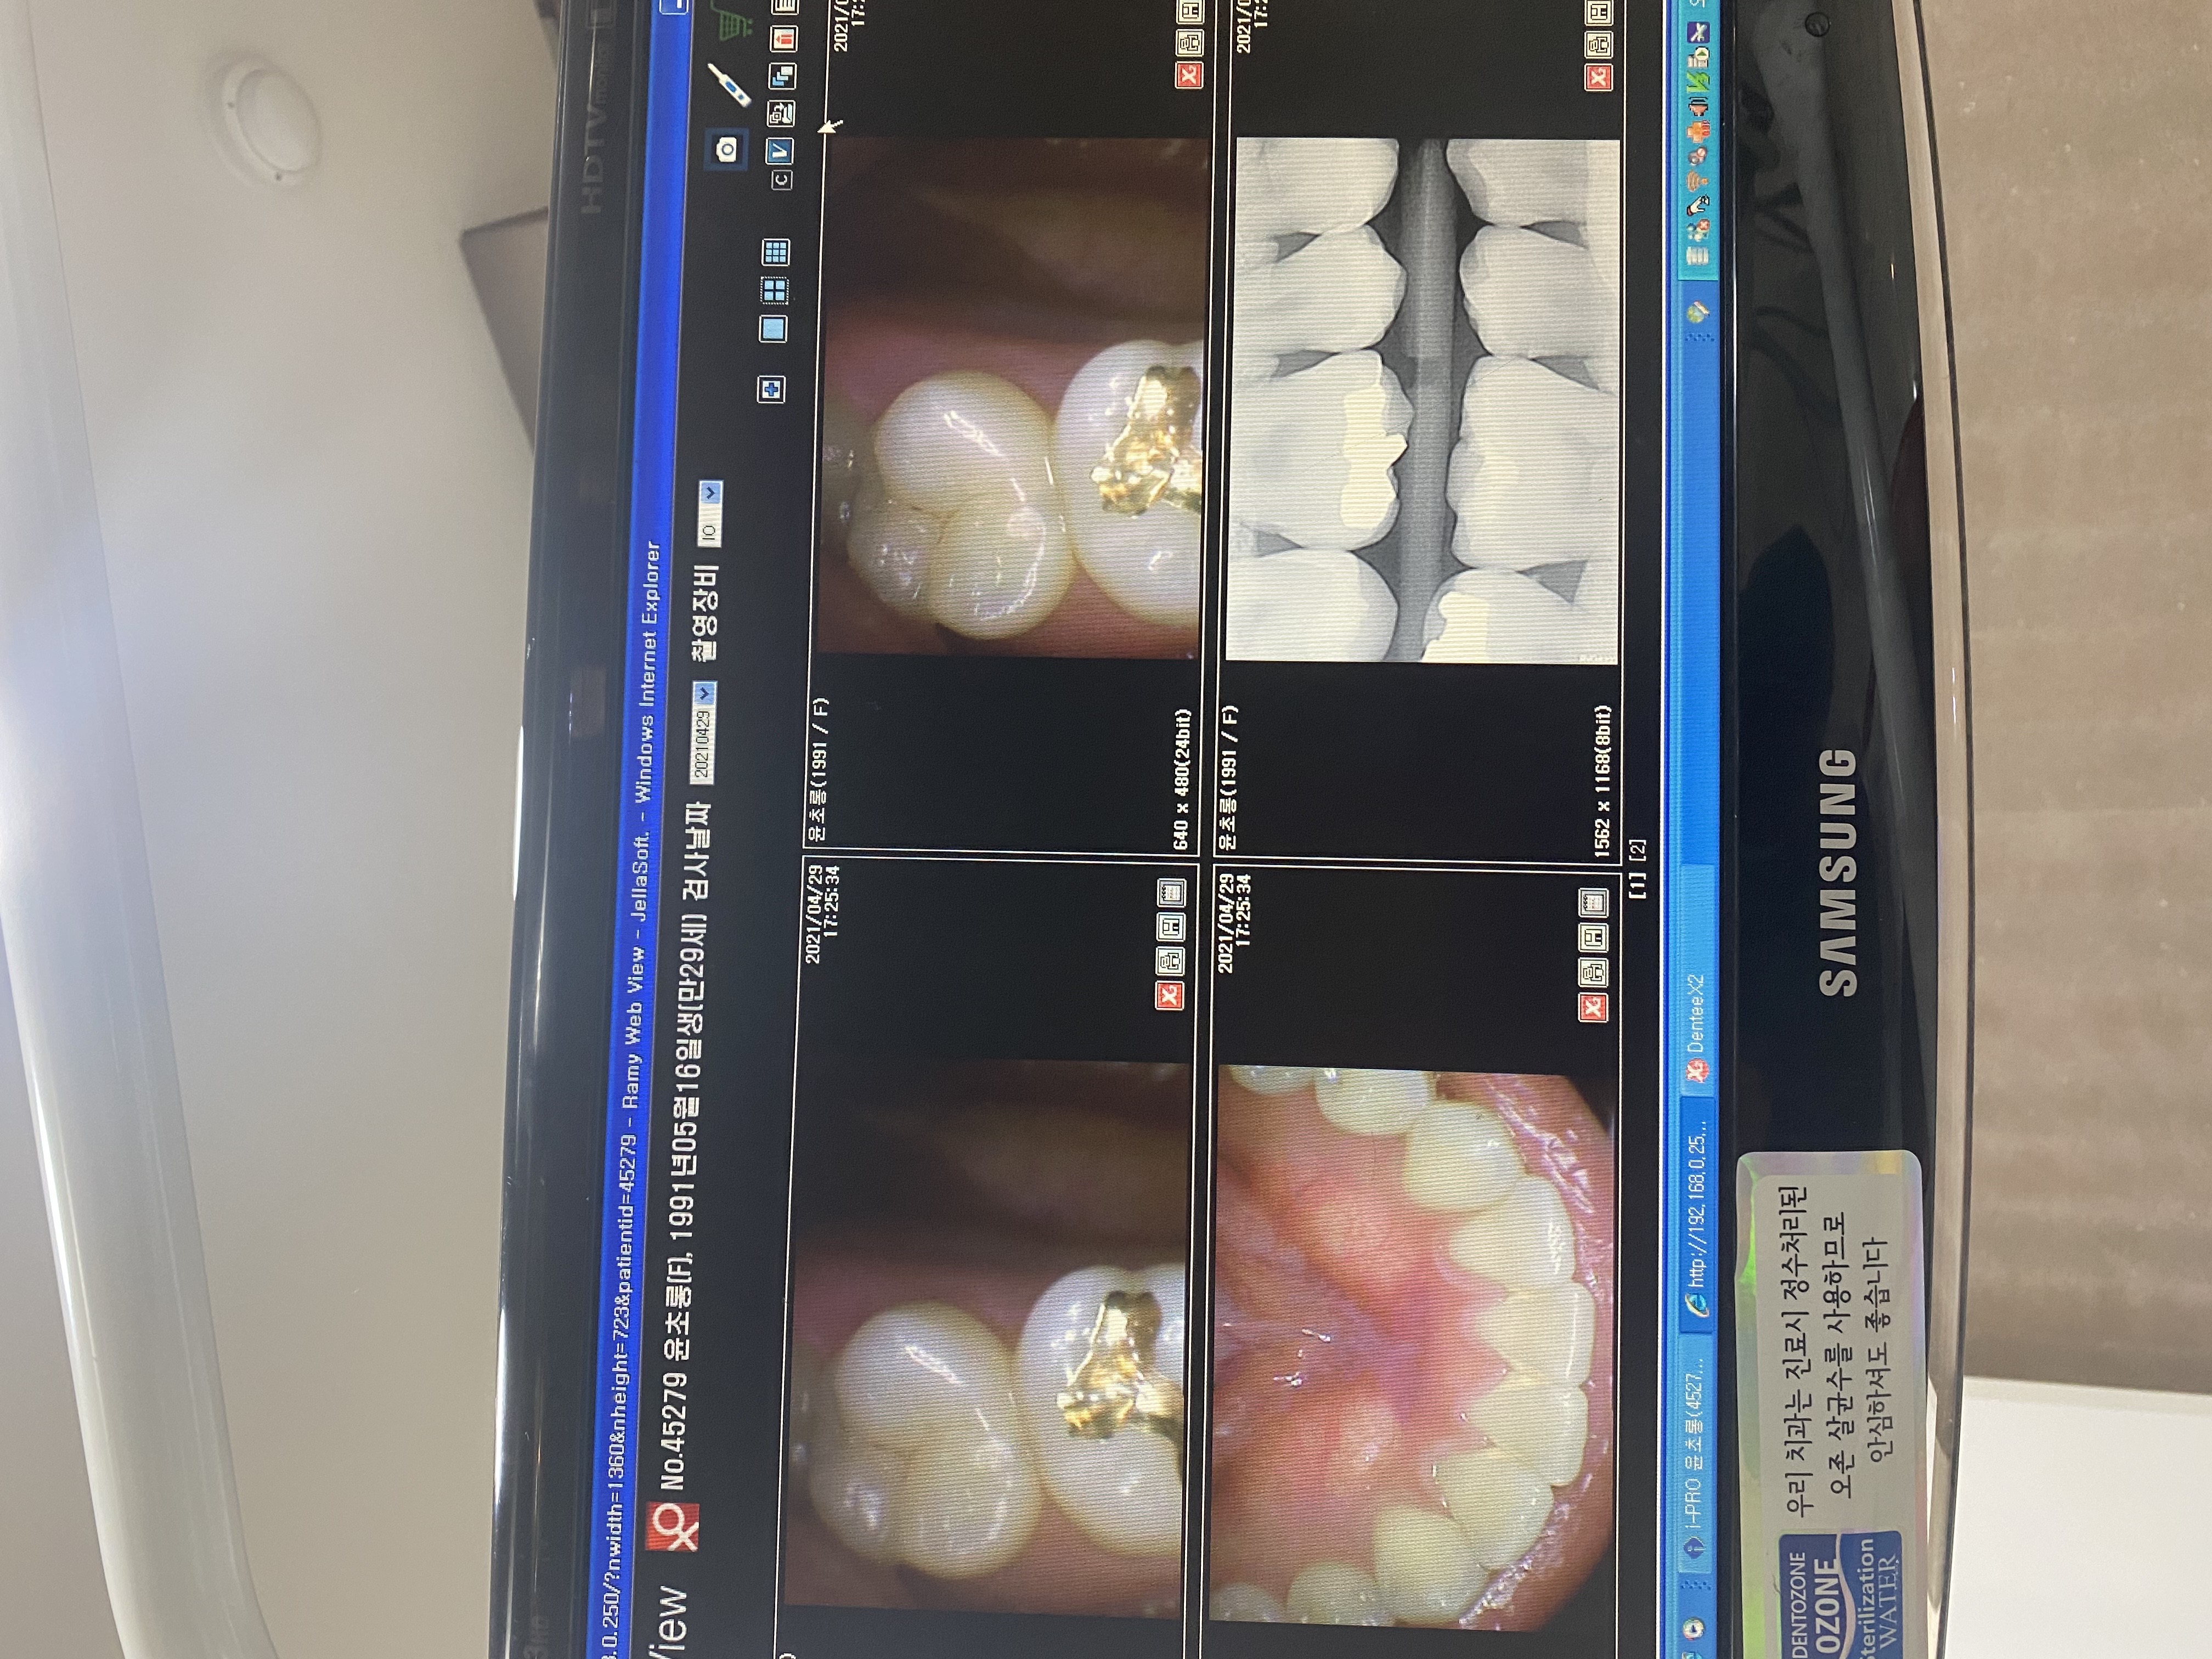

안녕하세요 선생님. 몇해전 선생님 조언으로 많은 도움을 받았었습니다. 이번에 가족이 통증이 있어 치과에 방문했는데 신경치료 또는 임플란트를 추천하더라고요. 제가보기에는 문제의 치아보면 치아부분에는 검게변하지 않아서 충치가 안보이는거 같은데 병원에서는 신경치료나 임플란트를 권하네요. 뿌리끝에도 검은 부분이 없는거 같고요. 뿌리사이에는 검게 염증이 보이는거 같습니다. 사진상으로 정확한 진단은 힘드시겠지만 조언좀 부탁드립니다. 2년전 선생님 말씀대로 신경치로안받고 저도 별다른 통증없이 잘 관리하면서 치아를 사용하고 있어서 항상 감사드립니다.